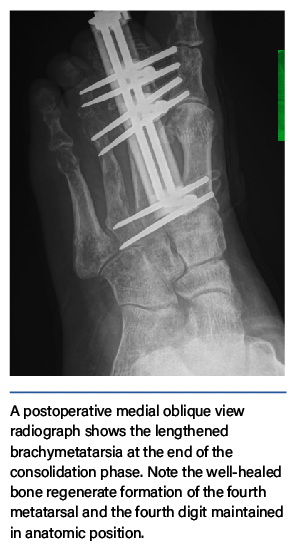

Surgeons have utilized various techniques for acute and gradual metatarsal lengthening, although there are documented complications.1–8 A commonly encountered complication of metatarsal lengthening is metatarsophalangeal joint (MTPJ) stiffness or dislocation/subluxation. To prevent this complication, utilize bridging of the external fixation across the MTPJ during gradual callus distraction.9 In limb lengthening surgery, surgeons have long utilized the concept of bridging the joint to minimize postoperative joint stiffness and contracture.9

Greater lengthening of the bone predisposes the joint to greater forces, which increases the risk of joint subluxation, chondrolysis, and postoperative joint stiffness. Performing the osteotomy farther from the joint lessens the forces that act on the joint, making a proximal metataphyseal-diaphyseal junction ostetotomy preferable. Negative side effects such as cartilage injury to the joint and stiffness in the MTPJ—regardless of how long an axial pin is maintained—can arise when one uses axial pinning to stabilize the digit to the metatarsal head. To prevent postop subluxation, stiffness, and chrondrolysis, the senior author developed a technique of spanning and protecting the MTPJ. The bridging fixator also provides acute digital deformity correction with simultaneous joint distraction, which maintains the long-term mobility of the MTPJ.9-11